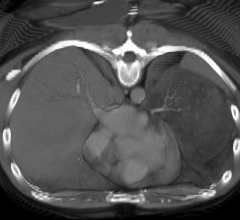

August 3, 2022 — Structural differences in lung airways between men and women may be the cause of differences in chronic ...